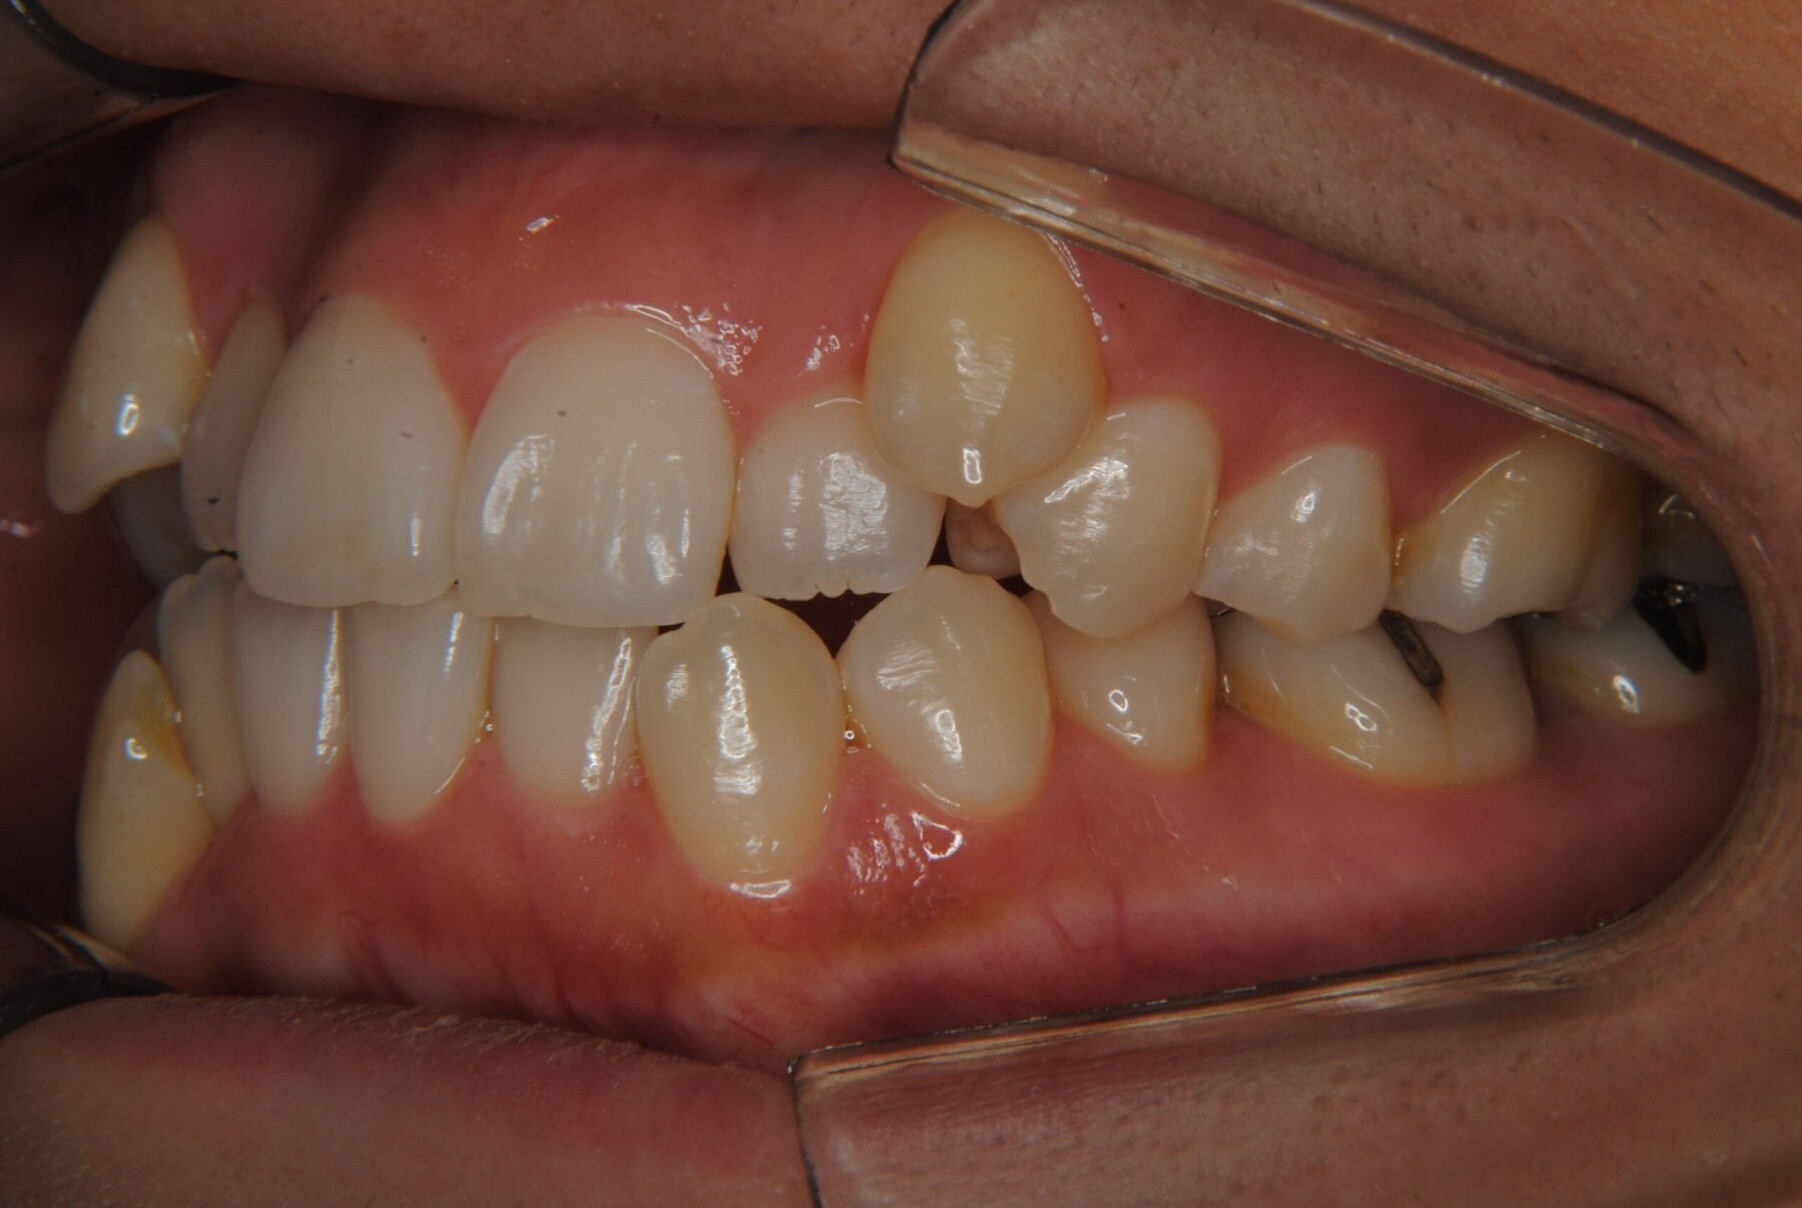

①主訴:八重歯、前歯のガタガタ、真ん中の不一致を治したい

②診断名:AngleⅠ級叢生

④治療に用いた主な装置:マルチブラケット装置(T21ブラケット)

⑤抜歯部位:上下左右第一小臼歯